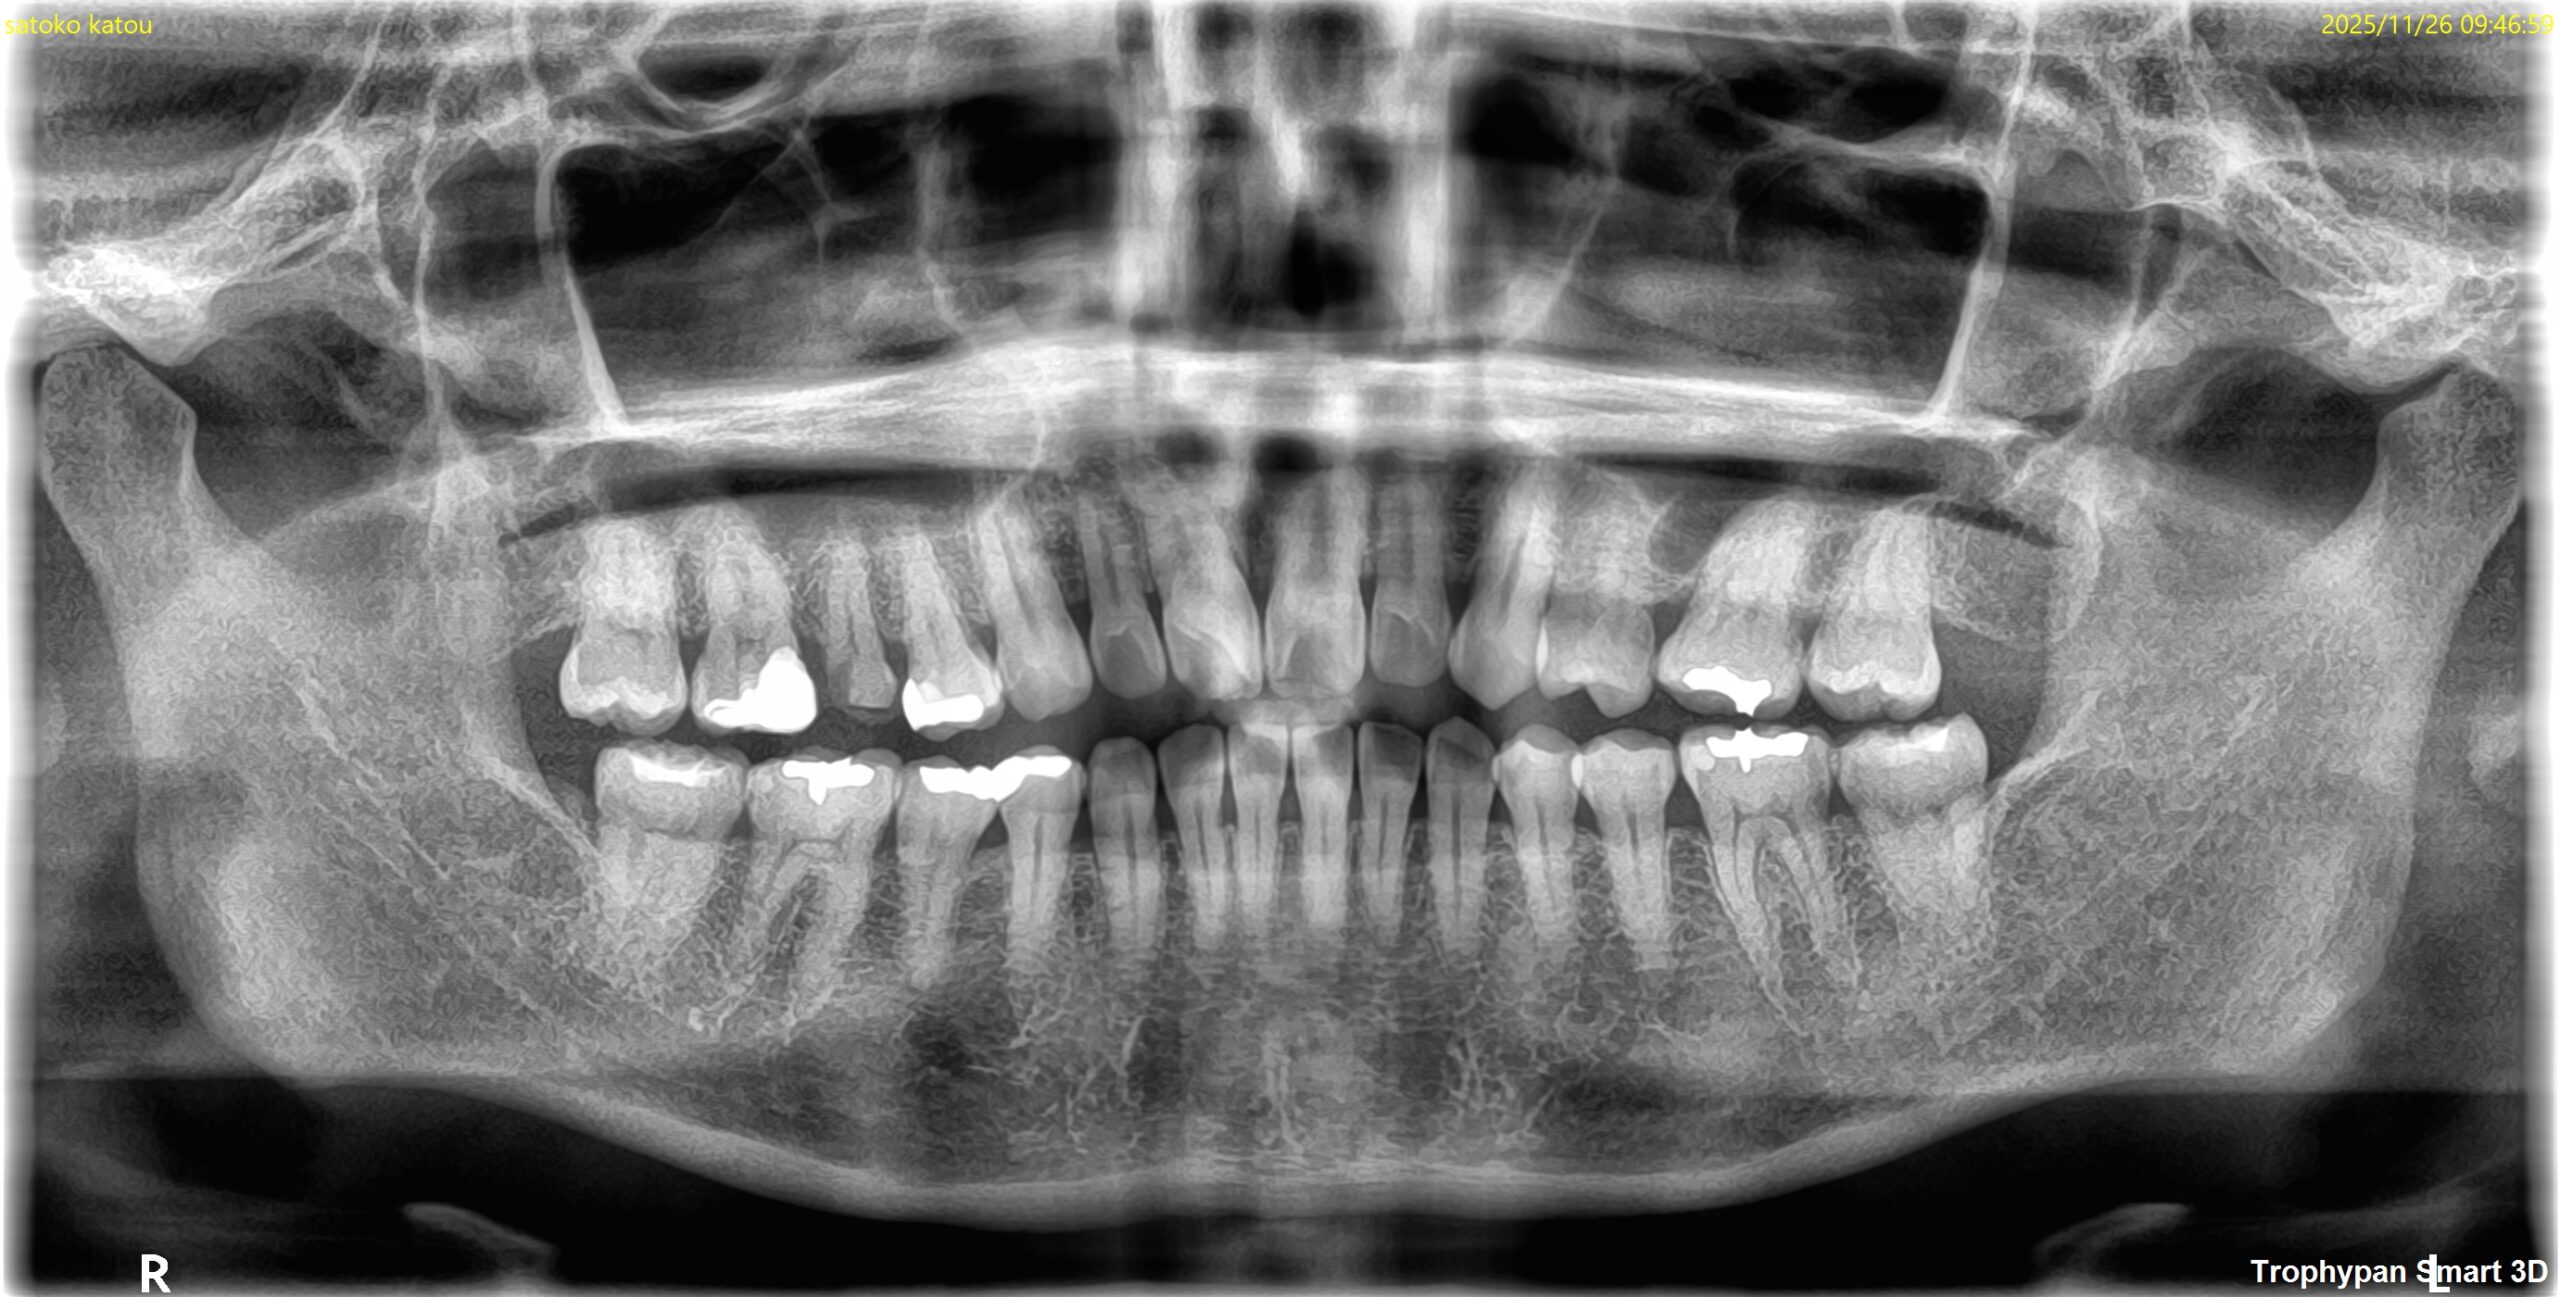

Pre-op Endo test(2025.11.26)

#4に咬合痛があるような…ないようなという感じであった。

病変のない、Initial RCTだ。

Pulp Dx: Asymptomatic irreversible pulpitis

Periapical Dx: Symptomatic apical periodontitis

Recommended Tx: RCT

術後にPA, CBCTを撮影した。